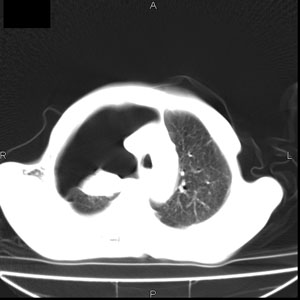

患者男,77岁,于3日前从树上摔下,头部查ct示蛛血,硬膜下出血,上腹部ct未见明显异常,右侧胸腔积液,左侧如常。肺部拍片示右侧肋骨多发骨折住院后今日来查肺部ct,我看到的是1。右侧胸腔血气胸并右肺上叶,中叶压缩性肺不张,2。右肺下叶肺挫伤并多发肋骨骨折,肌内及皮下积气3。左侧少量胸腔积液,我想请教的是3天前左侧胸腔里没有积液今天怎么出现了呢,是什么原因呢?请讨论。

有肺挫裂伤,有渗出,

回复楼主   左侧液气胸,液体来源1、肯定有血液成分,多少不一定。2、胸膜腔渗液,由于肺压缩、活动度下降,肯定胸膜吸收有问题,导致积液增多。

因为3天前病人刚摔的时候,左侧胸腔受伤不严重,故而当时没有胸腔积液,但病人受到这么大的伤害,胸膜腔内的液体动态平衡肯定会受到影响,所以过一段时间后才出现胸腔积液。

1、外伤出血需要一定的时间

2、气胸存在时间长了,产生的胸膜渗液

考虑外伤性迟发性胸腔积液。

右侧液气胸,胸膜创伤、肺组织挫伤,渗出属正常反应。